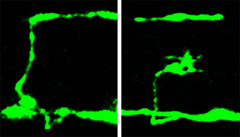

Nerve cells glow fluorescent green in these microscope photographs showing part of a cross section of a tiny nematode worm. The horizontal green linear feature near the bottom of each photo is the worm equivalent of the spinal cord, while a secondary nerve cord is the horizontal green line near the top. The vertical green line in the left photo is an unbroken axon, the long, wire-like portion of a single nerve cell. The right photograph shows how the nerve cell has broken in a mutant worm lacking a protein needed to make nerves flexible. The object at the end of the broken nerve is a "growth cone," which is evidence the broken nerve is attempting to repair itself.

The researchers used microscopes to photograph nerve-cell axons by inserting a jellyfish gene into the worms to make the worms’ neurons glow fluorescent green.

The biologists found breaks as well as branching or inappropriate new growth cones – signs of nerve-repair attempts – in places where a nerve cell body sent an axon from one side of the worm to the other, making the axon and any damage easy to see.